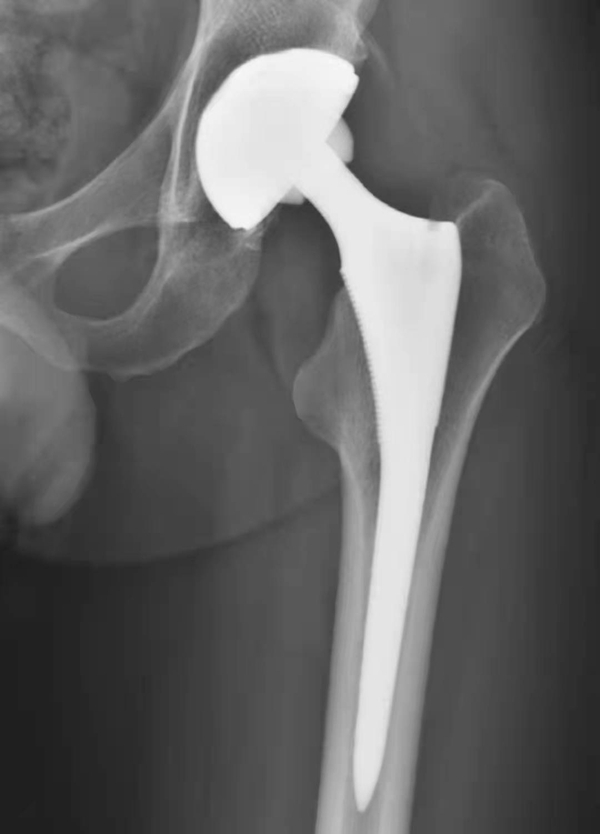

图1 人工髋关节置换术后正常X线表现